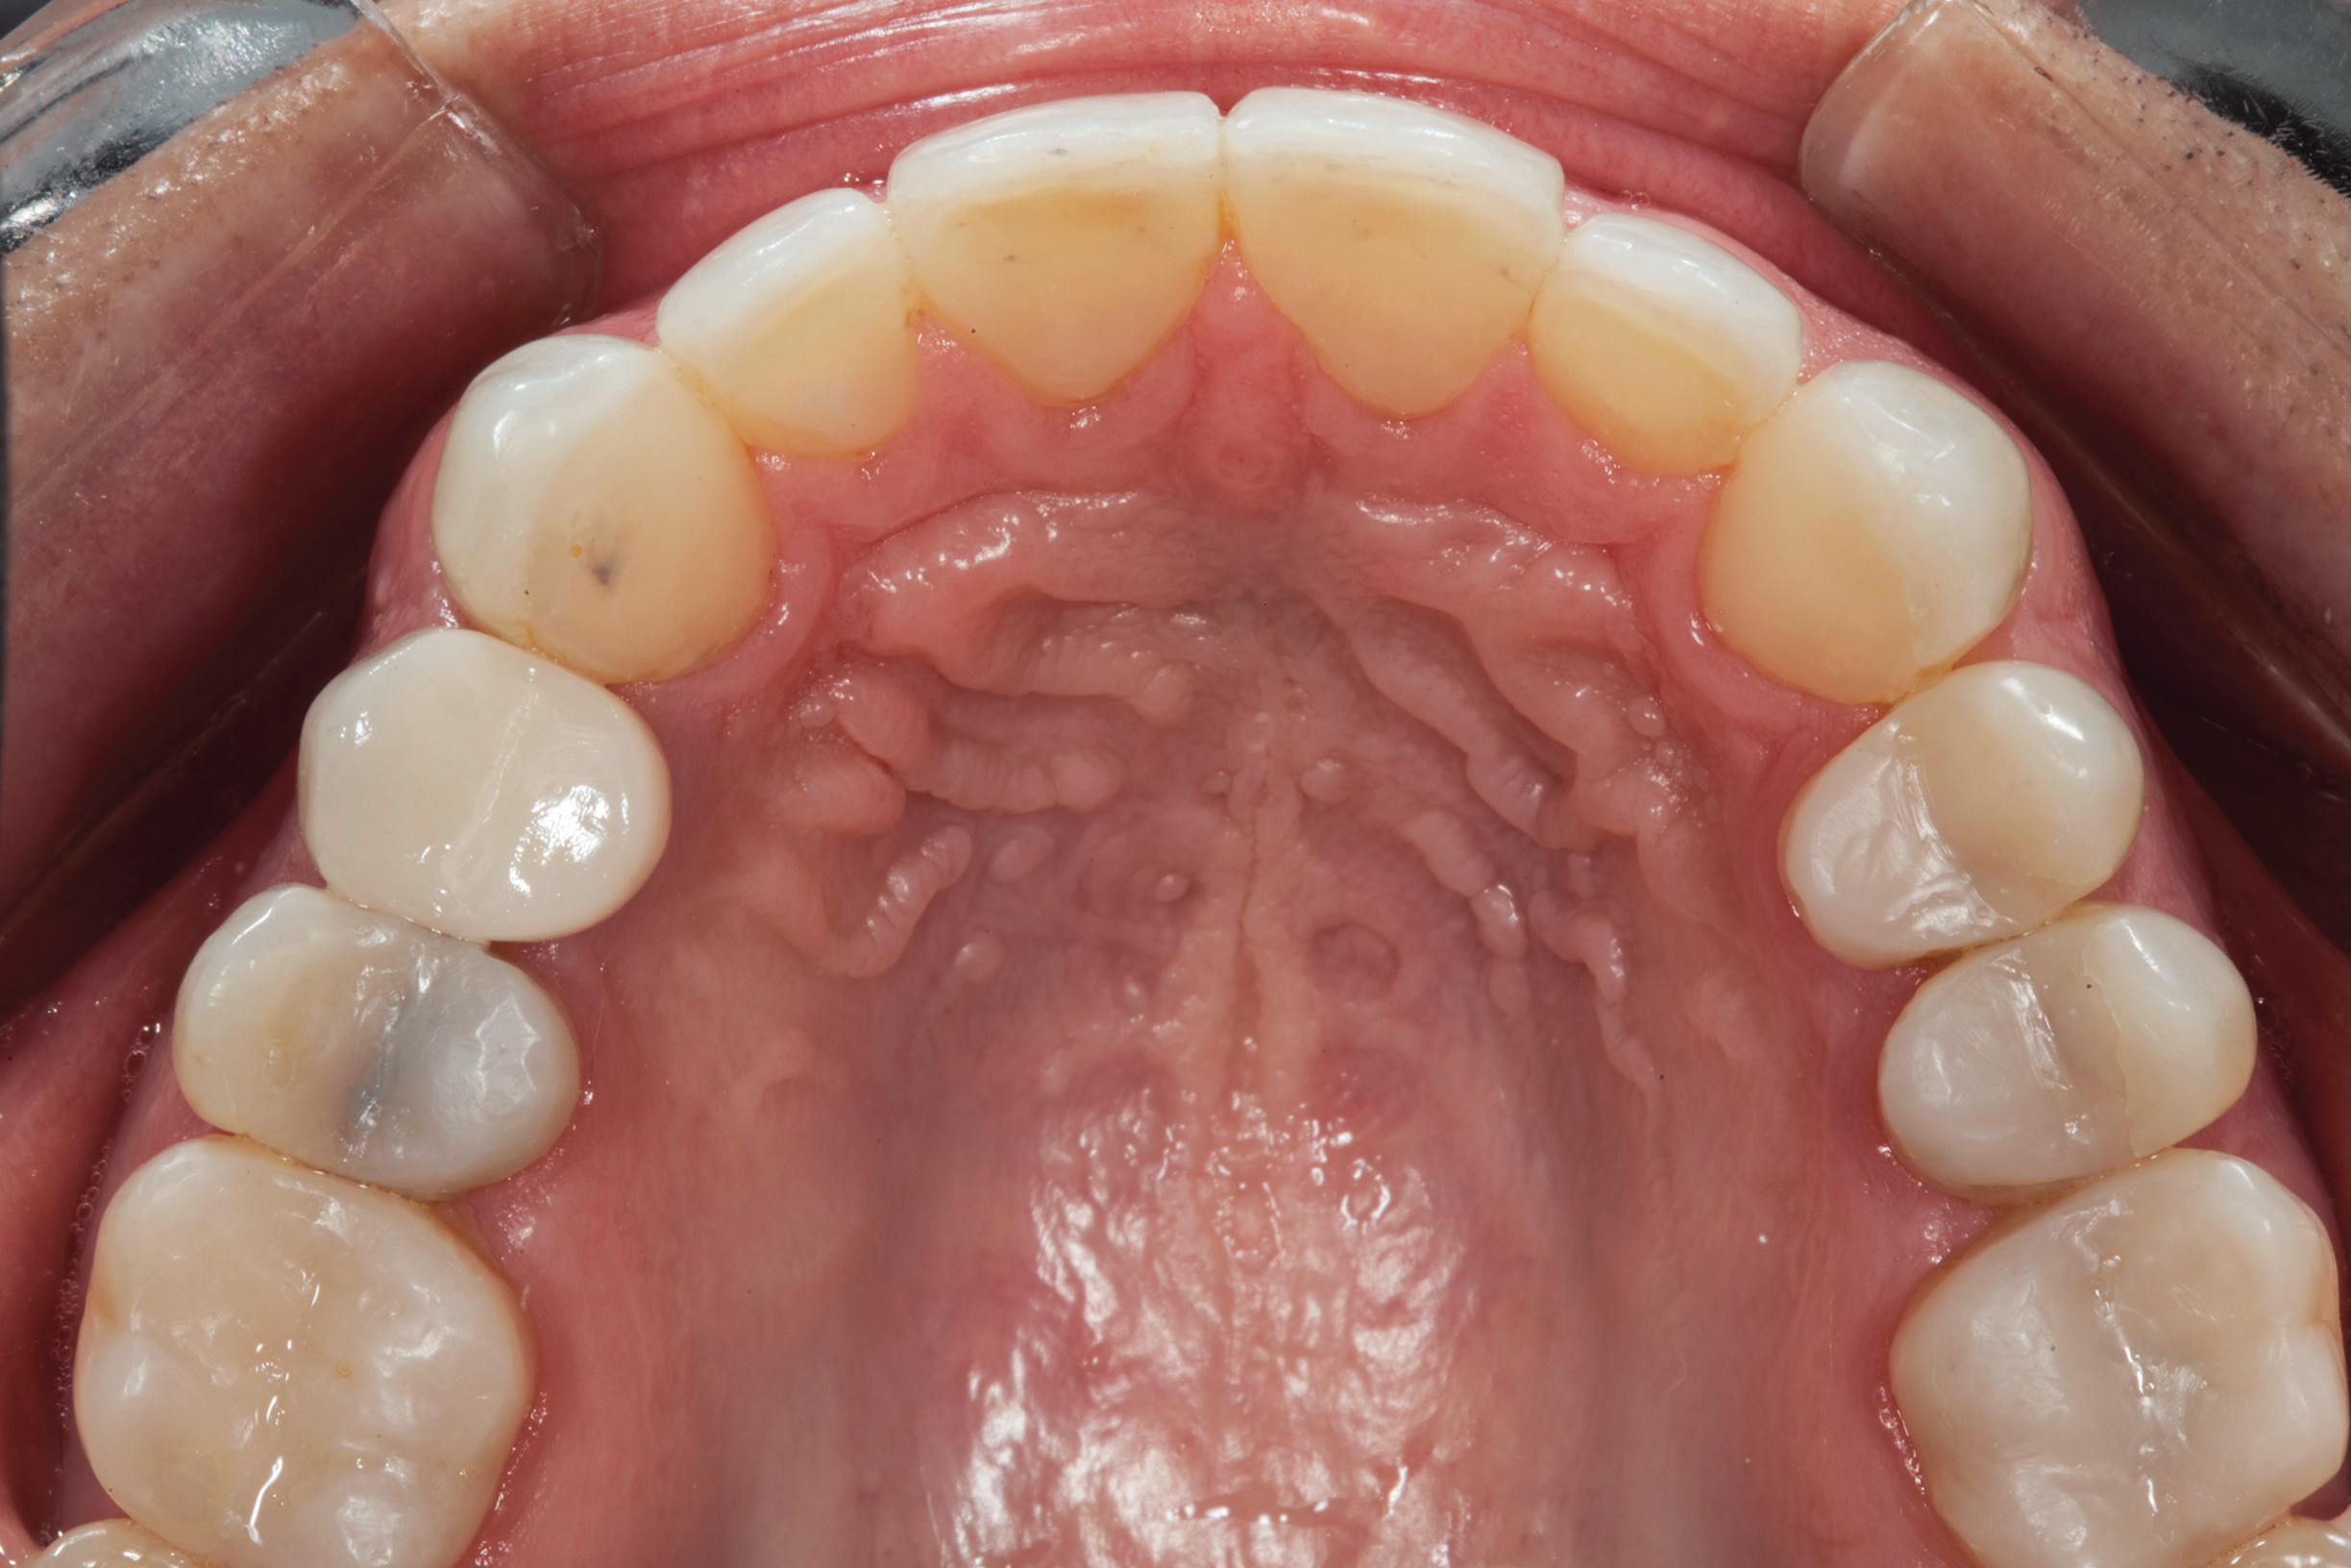

(4.) Preoperative occlusal view of upper arch.

Figure 4